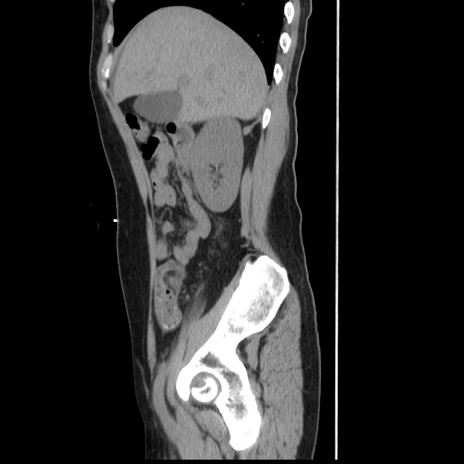

症例10(矢状断像)

【症例】 50歳代女性

【主訴】 腹痛

【現病歴】前日生レバーを食べた。今朝に排便あり。 昼前に突然発症の腹痛を生じ、当院救急外来を受診した。

【既往歴】 子宮筋腫にてで子宮全摘後

【身体所見】 意識清明、腹部:平坦、軟、下腹部やや左を中心に圧痛・反跳痛あり、筋性防御あり

【データ】WBC 7800、CRP 0.07